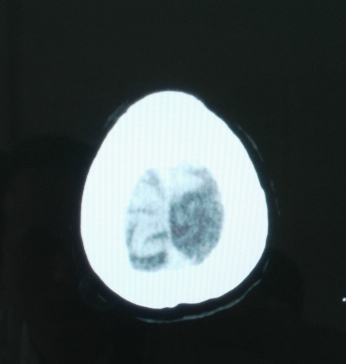

建议mr检查

局部脑沟有变化,建议强化,不除外血管畸形或转移性病变.

左顶叶不规则低密度灶后缘隐约见略高密度影,软化灶不能完全解释,建议增强检查或mai检查。

位置表浅 ct值28-31 建议增强或mr检查